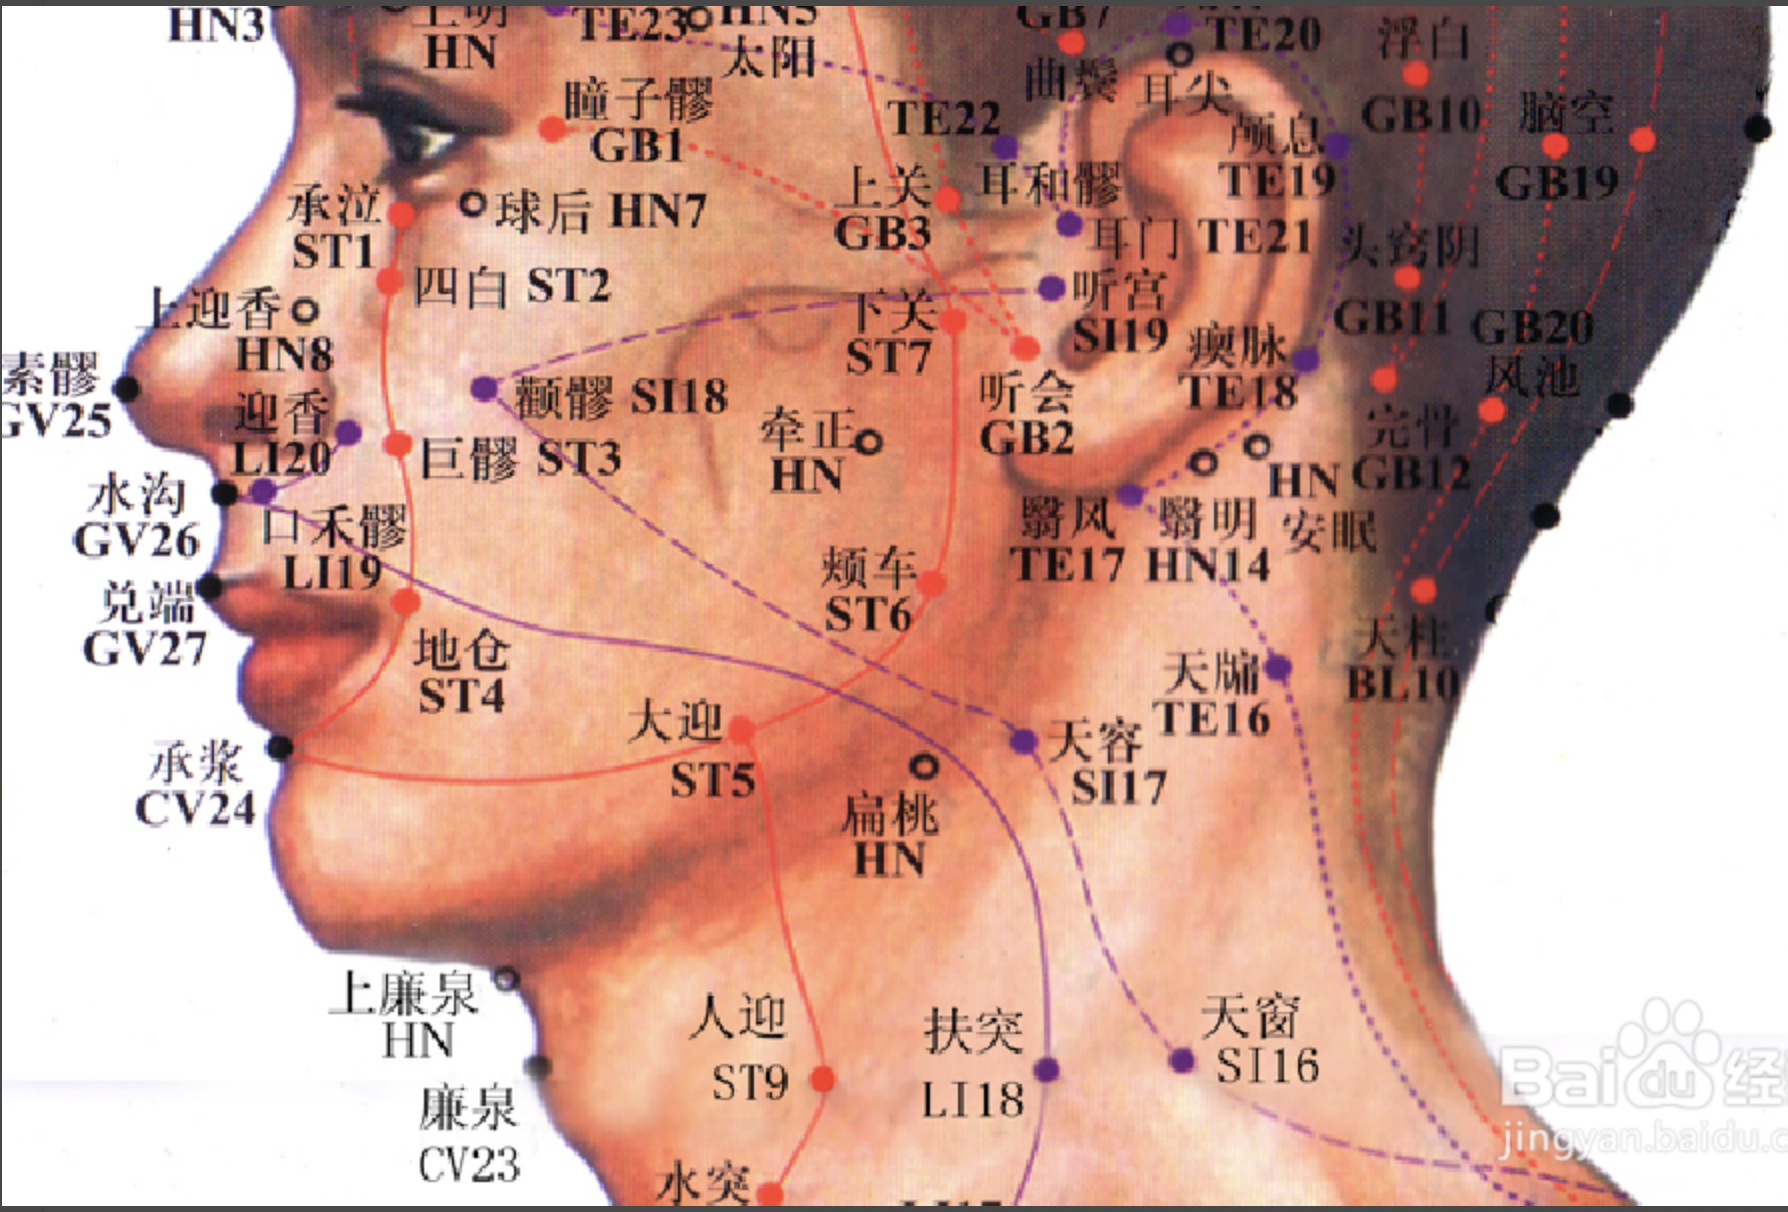

【(七)足太阳膀胱经(图 10-25-1)】

2、歌诀 足太阳经六十七,精明目内红肉藏,攒竹眉冲与曲差,五处上寸半承光,通天络却玉枕昂,天柱后际大筋外,大杼(zhù)背部第二行,风门肺俞厥阴四,心俞督俞膈俞强,肝胆脾胃俱挨次。三焦肾气海大肠,关元小肠到膀胱,中膂(lǚ)白环仔细量,自从大杼至白环,各各节外寸半长,上髎次髎中复下,一空二空腰髁当,会阳阴尾骨外取,附分侠脊第三行,魄户膏肓与神堂。噫嘻膈关魂门九,阳纲意舍仍胃仓。肓门志室胞肓续,二十椎下秩边场,承扶臀横纹中央,殷门浮郗到委阳,委中合阳承筋是,承山飞扬踝附阳。昆仑仆参连申脉,金门京骨束骨忙,通谷至阴小指旁。

3、经脉循行 起于目内眦,上额交会于于巅顶(百会)。

巅顶部支脉:从头顶到颞(niè)颥(rú)部。

巅顶部直行的脉:从头顶入里联络于脑,回出分开下行项后,沿肩胛部内侧,夹脊柱,到达腰部,从脊旁肌肉进入体腔联络肾脏,属于膀胱。

腰部支脉:向下通过臀部,进入腘(guó)窝内。

后项部支脉:通过肩胛骨内缘直下,经过臀部下行,沿大腿后外侧与腰部下来的支脉会和于腘窝中。从此向下,出于外踝后,第五趾骨粗隆,至小指外侧端(至阴),与足少阴经相接。

4、主要病候 小便不通,遗尿,癫狂,疟疾,目痛,见风流泪,鼻塞多涕,鼻衄,头痛,项、背、臀部及下肢循行部位痛麻等。

3、主治概要 主治头、项、目、背、腰、下肢部病证及神志病,背部第一侧线的背俞穴及第二侧线相平的腧穴,主治与其相关的脏腑病证和有关的组织器官病证。

晴明

【定位】 在面部,目内眦角稍内上方凹陷处(图 10-25-2)。

【主治】 目赤肿痛,流泪,视物不明,目眩,近视,夜盲,色盲。

【配伍】 配球后、光明治视物不明。

【刺灸法】 嘱患者闭目,医者左手轻推轻推眼球向外侧固定,右手缓慢进针,紧靠眶缘直刺 0.5 ~ 1 寸。不捻转,不提插(或之轻微地捻转和提插)。出针后按压针孔片刻,以防出血。本穴禁灸。

【附注】 手足太阳、足阳明、阴跷、阳跷五脉交会穴。

攒竹

【定位】 在面部,当眉头凹陷处,约在目内眦直上(图 10-25-2)。

【主治】 头痛 ,口眼歪斜,目视不明,流泪,目赤肿痛,眼睑瞤(rún)动,眉棱骨痛,眼睑下垂。

【配伍】 配阳白治口眼歪斜、眼睑下垂。

【刺灸法】 平刺 0.5 ~ 0.8 寸。禁灸。

天柱

【定位】 在项部大筋(斜方肌)外缘之后发际凹陷中,约当后发际正中旁开 1.3 寸。

【主治】 头痛,项强,鼻塞,癫狂痫,肩背病,热病。

【配伍】 配大椎治头痛项强。

【刺灸法】 直刺或斜刺 0.5 ~ 0.8 寸,不可向内上方深刺,以免伤及延髓。